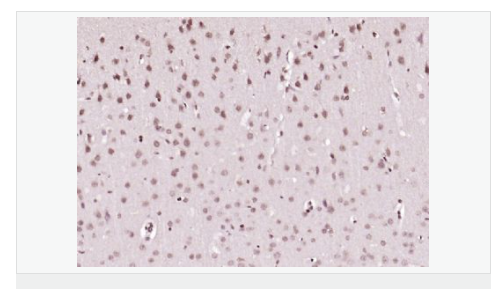

| 產品應用 | ELISA=1:5000-10000 IHC-P=1:100-500 IHC-F=1:100-500 IF=1:100-500 (石蠟切片需做抗原修復) not yet tested in other applications. optimal dilutions/concentrations should be determined by the end user. |

| 產品介紹 | The protein encoded by this gene is a member of the BTG/Tob family. This family has structurally related proteins that appear to have antiproliferative properties. This encoded protein might play a role in neurogenesis in the central nervous system. Two transcript variants encoding different isoforms have been found for this gene. [provided by RefSeq, Aug 2008]. Function: Overexpression impairs serum-induced cell cycle progression from the G0/G1 to S phase. Subunit: Interacts with KCNMA1 tetramer. There are probably 4 molecules of KCMNB1 per KCNMA1 tetramer. Subcellular Location: Membrane; Multi-pass membrane protein. Tissue Specificity: Abundantly expressed in smooth muscle. Low levels of expression in most other tissues. Within the brain, relatively high levels found in hippocampus and corpus callosum. Similarity: Belongs to the KCNMB (TC 8.A.14.1) family. KCNMB1 subfamily. SWISS: Q14201 Gene ID: 10950 Database links: Important Note: This product as supplied is intended for research use only, not for use in human, therapeutic or diagnostic applications |